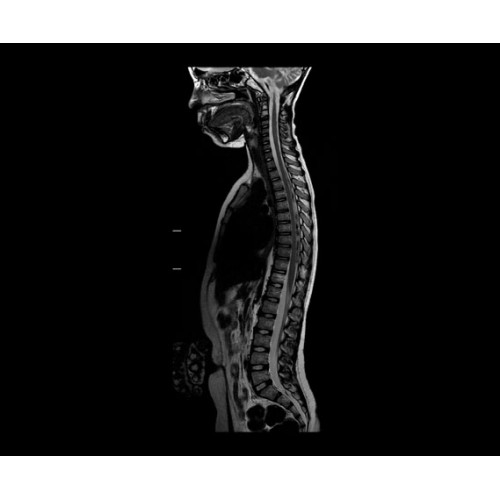

SIGNA PET/MR 3.0T — это гибридная система, в которой совмещаются две принципиально разные технологии — магнитно-резонансную томографию (МРТ) и позитронно-эмиссионную томографию (ПЭТ). Система отличающийся высокой чувствительностью и эффективностью и предназначена для диагностики в области онкологии, неврологии, кардио-васкулярных исследований, исследований воспалительных процессов.

Компания GE Healthcare представляет революционную, полностью интегрированную систему SIGNA PET/MR1, в которой сочетаются времяпролетная технология (TOF) и возможности напряженности магнитного поля 3.0 Тл. Мы поможем вам поднять исследования на более высокий уровень. SIGNA PET/MR позволяет достичь впечатляющей точности и скорости исследований, а благодаря новейшей технологии реконструкции Q.Clear2 качество изображений улучшается в два раза. Кроме того, в систему включен полный набор клинических приложений и гибких катушек для проведения любых видов исследования, открывая для вас возможности визуализации, о которых вы даже не догадывались.

Кроме того, в результате использования технологии TOF и инновационной технологии реконструкции Q.Clear вы сможете добиться прекрасного соотношения сигнал/шум. А благодаря технологии нулевого времени эхо (ZTE) визуализировать костную структуру без ионизирующего излучения. Все эти разработки для улучшения качества сканирования и точности анализа помогут вам использовать весь потенциал ПЭТ/МРТ.

• МРТ с функцией нулевого времени эхо (ZTE) отличается точностью, возможностью персональных настроек и отсутствием ионизирующего излучения. Она приходит на смену традиционному исследованию на основе рентгеновского излучения. МРТ с функцией нулевого времени эхо (ZTE) на базе SIGNA ПЭТ/МРТ является более надежной и быстрой по сравнению с системами, использующими сверхмалое время эхо (UTE).